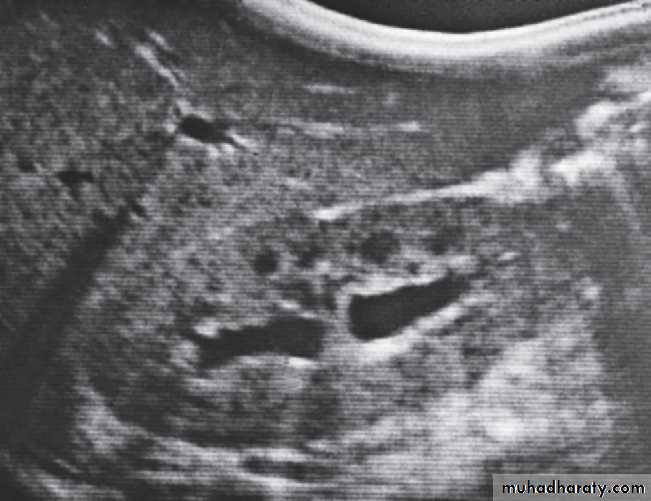

U/S :Most renal calculi of more than 5 mm in size are readily seen at ultrasound, produce intense echoes and cast acoustic shadows.

Stones in the ureters cannot be excluded on ultrasound, although stones lodged at the vesicouteric junction may be demonstrated .

Ultrasound, TCCs can be difficult to see because they blend with the renal sinus fat, although large tumours can usually be demonstrated as a central mass within the sinus .

Ultrasound may help to differentiate between a radiolucent stone and tumour, as the calculus demonstrates acoustic shadowing.